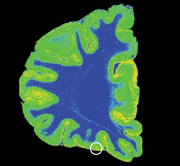

У людей, покончивших жизнь самоубийством, отмечаются анатомические и биохимические изменения в двух отделах головного мозга: в орбитальной префронтальной коре, расположенной над глазами, и в дорсальном ядре шва, находящемся в стволе мозга. Эти изменения указывают на снижение способности головного мозга к выработке и утилизации серотонина нейротрансмиттера, недостаток которого характерен для мозга импульсивных или страдающих тяжелыми депрессиями людей Серотонин вырабатывается нейронами дорсального ядра шва. По их длинным проекциям (синяя стрелка) он достигает орбитальной префронтальной коры. У жертв самоубийства дорсальное ядро шва снабжает орбитальную кору недостаточным количеством серотонина.

Изменения в орбитальной префронтальной коре

На срезах головного мозга видно, что орбитальная префронтальная кора (обведена кружком) мозга самоубийц содержит меньшее количество нейронов.

Серотониновые транспортеры (золотистый цвет) обеспечивают поглощение серотонина во всей массе коры. В участке коры, выделенной кружком, количество серотониновых транспортеров понижено.

В исследуемом участке коры (оранжевый цвет) обнаружено также повышенное связывание серотонина нейронами.